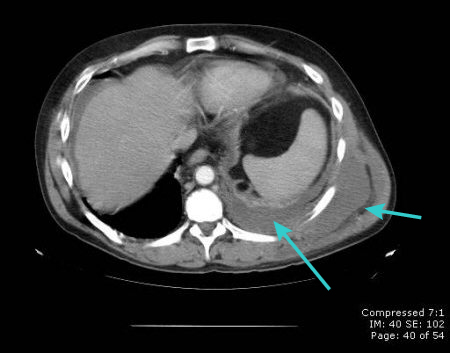

[Figure caption and citation for the preceding image starts]: CT scan showing large right pleural effusionFrom the collection of Dr Nicholas Maskell; used with permission [Citation ends].